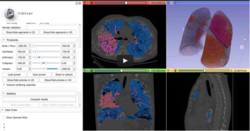

Slicer4 Lung CT Analyzer

• The LungCTAnalyzer tutorial and the LungCTAnalyzer video-based demo show how to visualize and quantify infiltration, emphysema and collapsed lung areas in CT datasets acquired on COVID-19 patients.

• Authors: Rudolph Bumm, MD, Andras Lasso, PhD.

• Audience: End-users

• Modules: LungCTSegmenter, LungCTAnalyzer

• Based on: 3D Slicer version 5.0 (4.11)